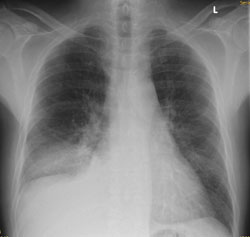

Radiologie Quiz 47

Ein 68-jähriger Patient mit chronischer Niereninsuffizienz und hypertensiver Herzerkrankung klagt akutell über zunehmende Dyspnoe. Sie veranlassen ein Thoraxröntgen.